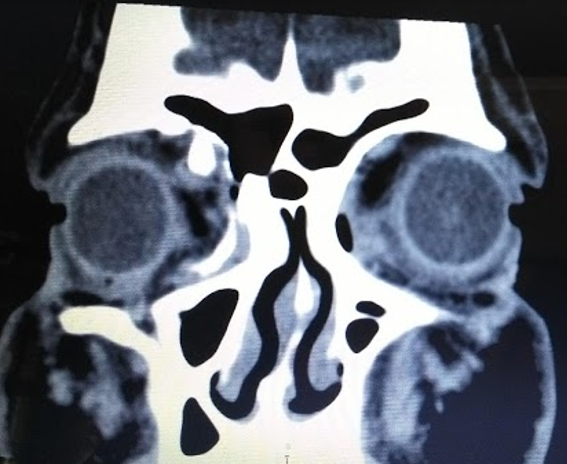

Paciente masculino de 49 años de edad procedente de área urbana refiere inicio de enfermedad actual de 1 día de evolución cuando presentó dolor y disminución de la agudeza visual posterior a trauma directo con objeto expedido a alta velocidad, por lo que consulta.